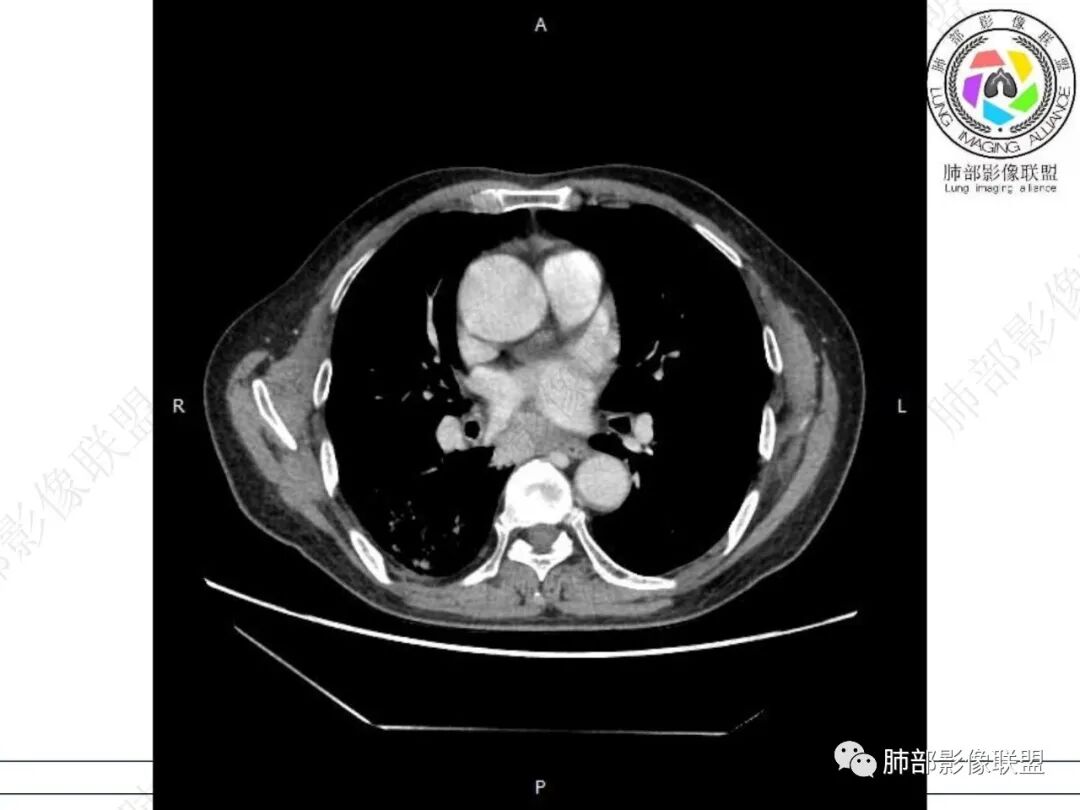

右肺下叶背段可见斑片状、条片状高密度影,支气管扩张,周围伴有磨玻璃影,边界欠清,纵隔窗:可见脊柱偏右侧可见斑片状影,与食管交界面欠清,食管形态不规则,考虑食管支气管瘘?食管异物穿孔?支气管异物?建议食管镜及支气管镜检查。

气管隆突下团片影,其内积气,与食道分界不清,食道壁增厚,管腔狭窄,右下肺实变影,支气管壁增厚,考虑食管支气管瘘并右下肺感染,食道肿瘤病变不除外

支持食管支气管瘘(考虑食管癌)伴后纵隔及右肺感染,食管管壁明显增厚,管腔狭窄,相邻右侧后纵隔内软组织内可见气体影,与食管分界不清,右肺有实变及不张。

右肺下叶背段条片状实变影,内可见支气管走行,支气管有狭窄有扩张,周围可见磨玻璃影,隆突下团片影,内密度不均可见气体影,与周围结构界限不清。食管下段壁增厚,管腔狭窄,右肺下叶慢性炎、肺不张,考虑食道肿瘤所致气管食管瘘。

右肺下叶沿肺叶肺段分布斑片、条片状影,以下叶背段为显,边缘模糊,内可见支气管走行,局部支气管管壁增厚,右侧胸腔少量积液。纵隔隆突下可见不均匀软组织密度影,与周围结构分界不清,内见气体密度影,与食管及相邻右肺支气管之间未显示通道。邻近食管下段壁明显不规则增厚,增强后食管管壁明显不均匀强化,可见线样强化的连续完整粘膜影。